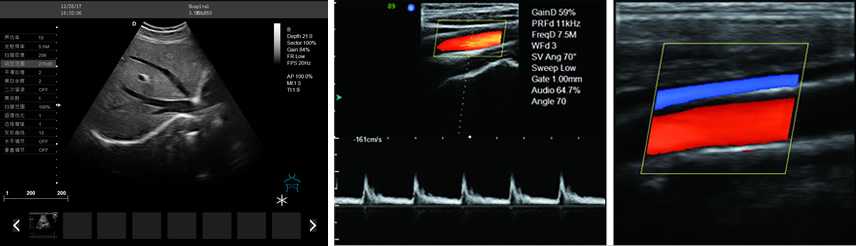

DW-PF522全數字彩色多普勒超聲診斷儀

產品性能:高集成數字式彩色多普勒技術,寬頻探頭,強勁的組合式模塊化軟件設計,全數字式大容量圖像存貯和文件歸檔管理,適用范圍:用于人體超聲診斷檢查。